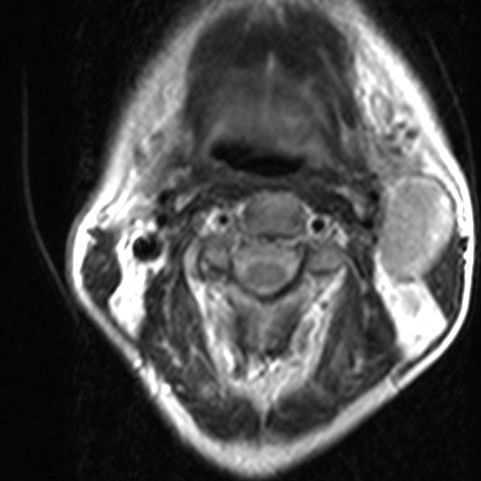

Tonsillentumor asymptomatisch. Das große Lymphknotenpaket am Unterkieferwinkel war aufgefallen.